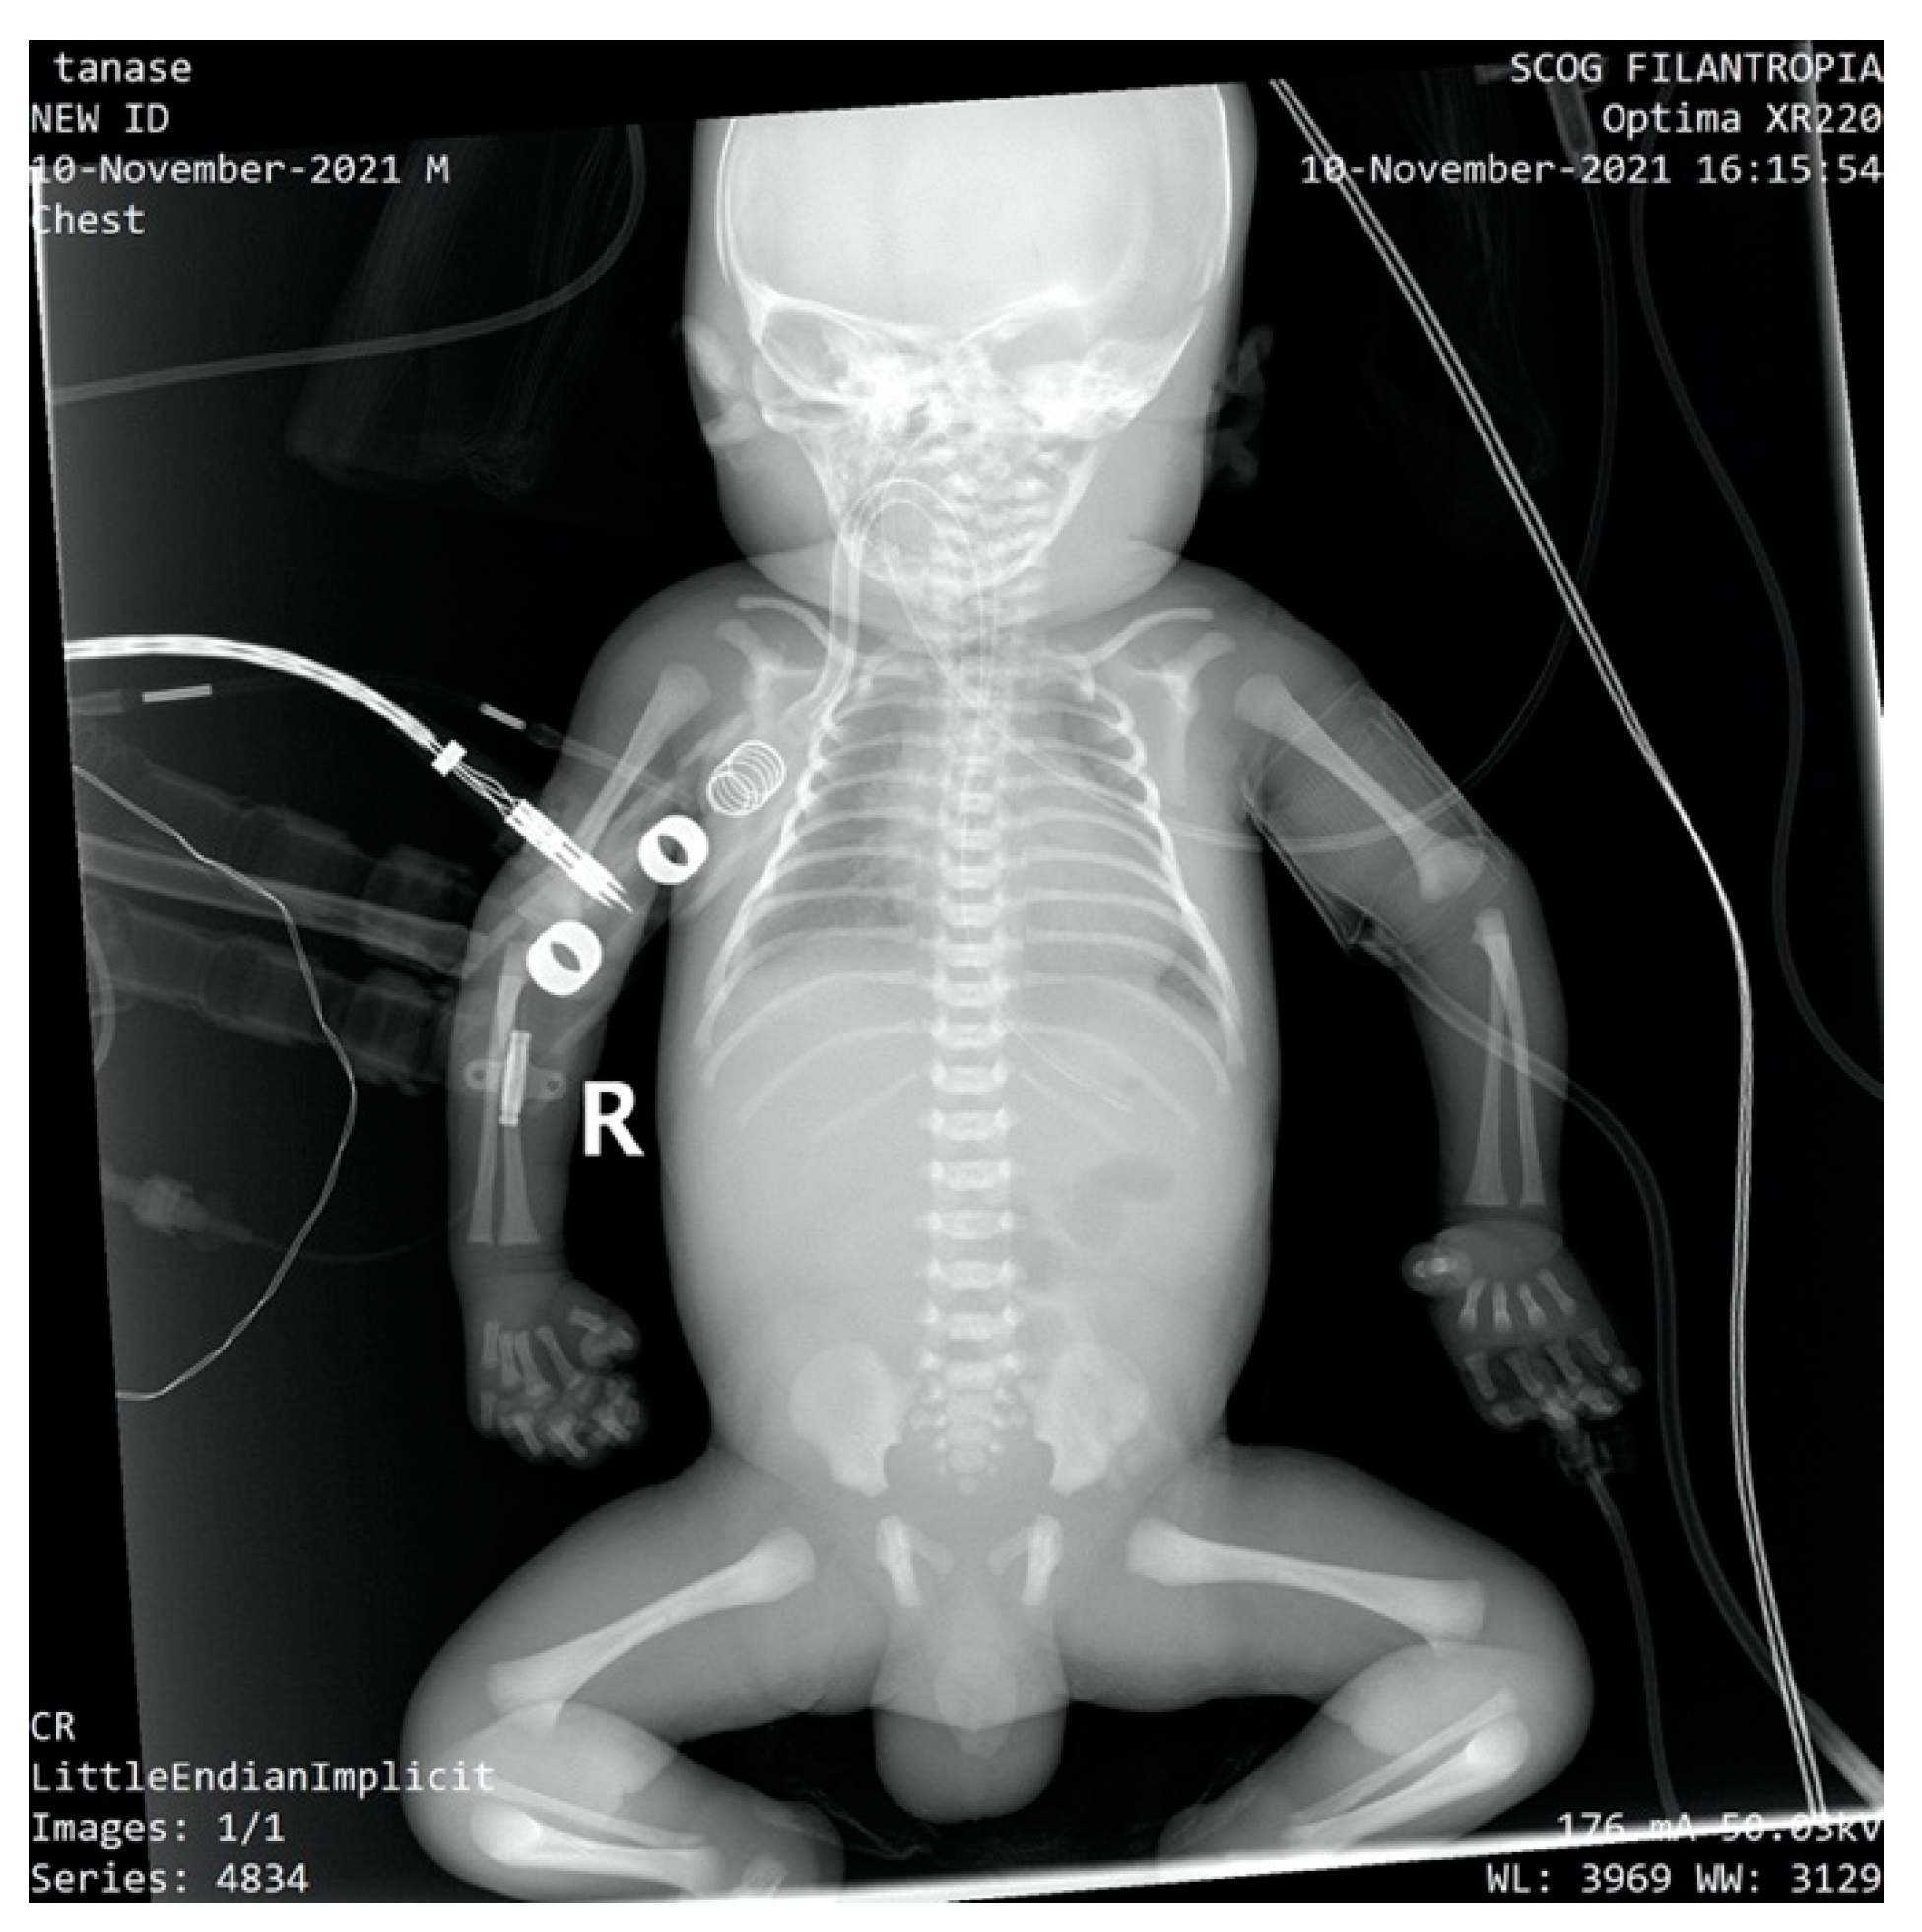

The newborn was admitted to the NICU with an extremely severe condition, pale skin, generalized edema with the appearance of hydrops, generalized purpura, ecchymosis of the cephalic extremity, parietooccipital cephalohematoma, abdomen with important wall edema and ascites fluid. Thoracoabdominal radiography and abdominal ultrasound showed the presence of ascites fluid and poor aeration of the colic frame (Figure 2).

Figure 2.

Thoraco-abdominal X-ray-poor aeration of the colic frame, ascites fluid.